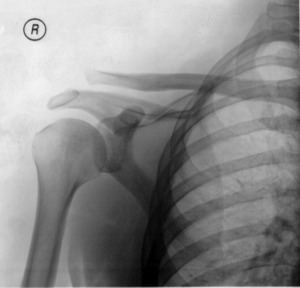

Type 3 AC joint separation on plain X ray

In a Type III AC separation both acromioclavicular and coracoclavicular ligaments are torn without significant disruption of the deltoid or trapezial fascia.[10] A significant bump, resulting in some shoulder deformity, is formed by the lateral end of the clavicle. This bump, caused by the clavicle's dislocation,[5] is permanent. The clavicle can be moved in and out of place on the shoulder. A radiographic examination will show the results as abnormal.